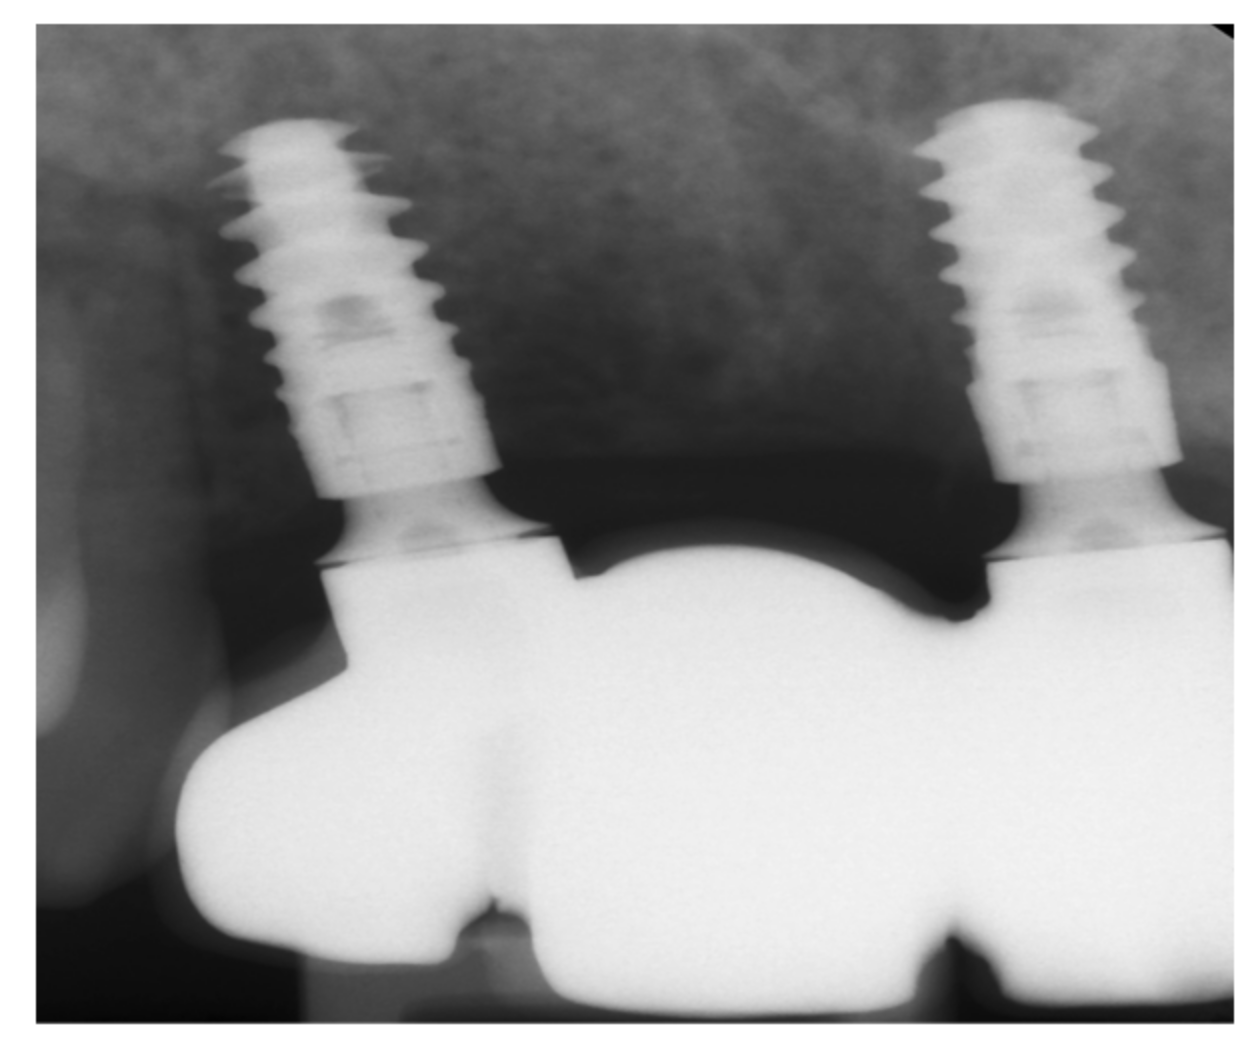

2. Case Report